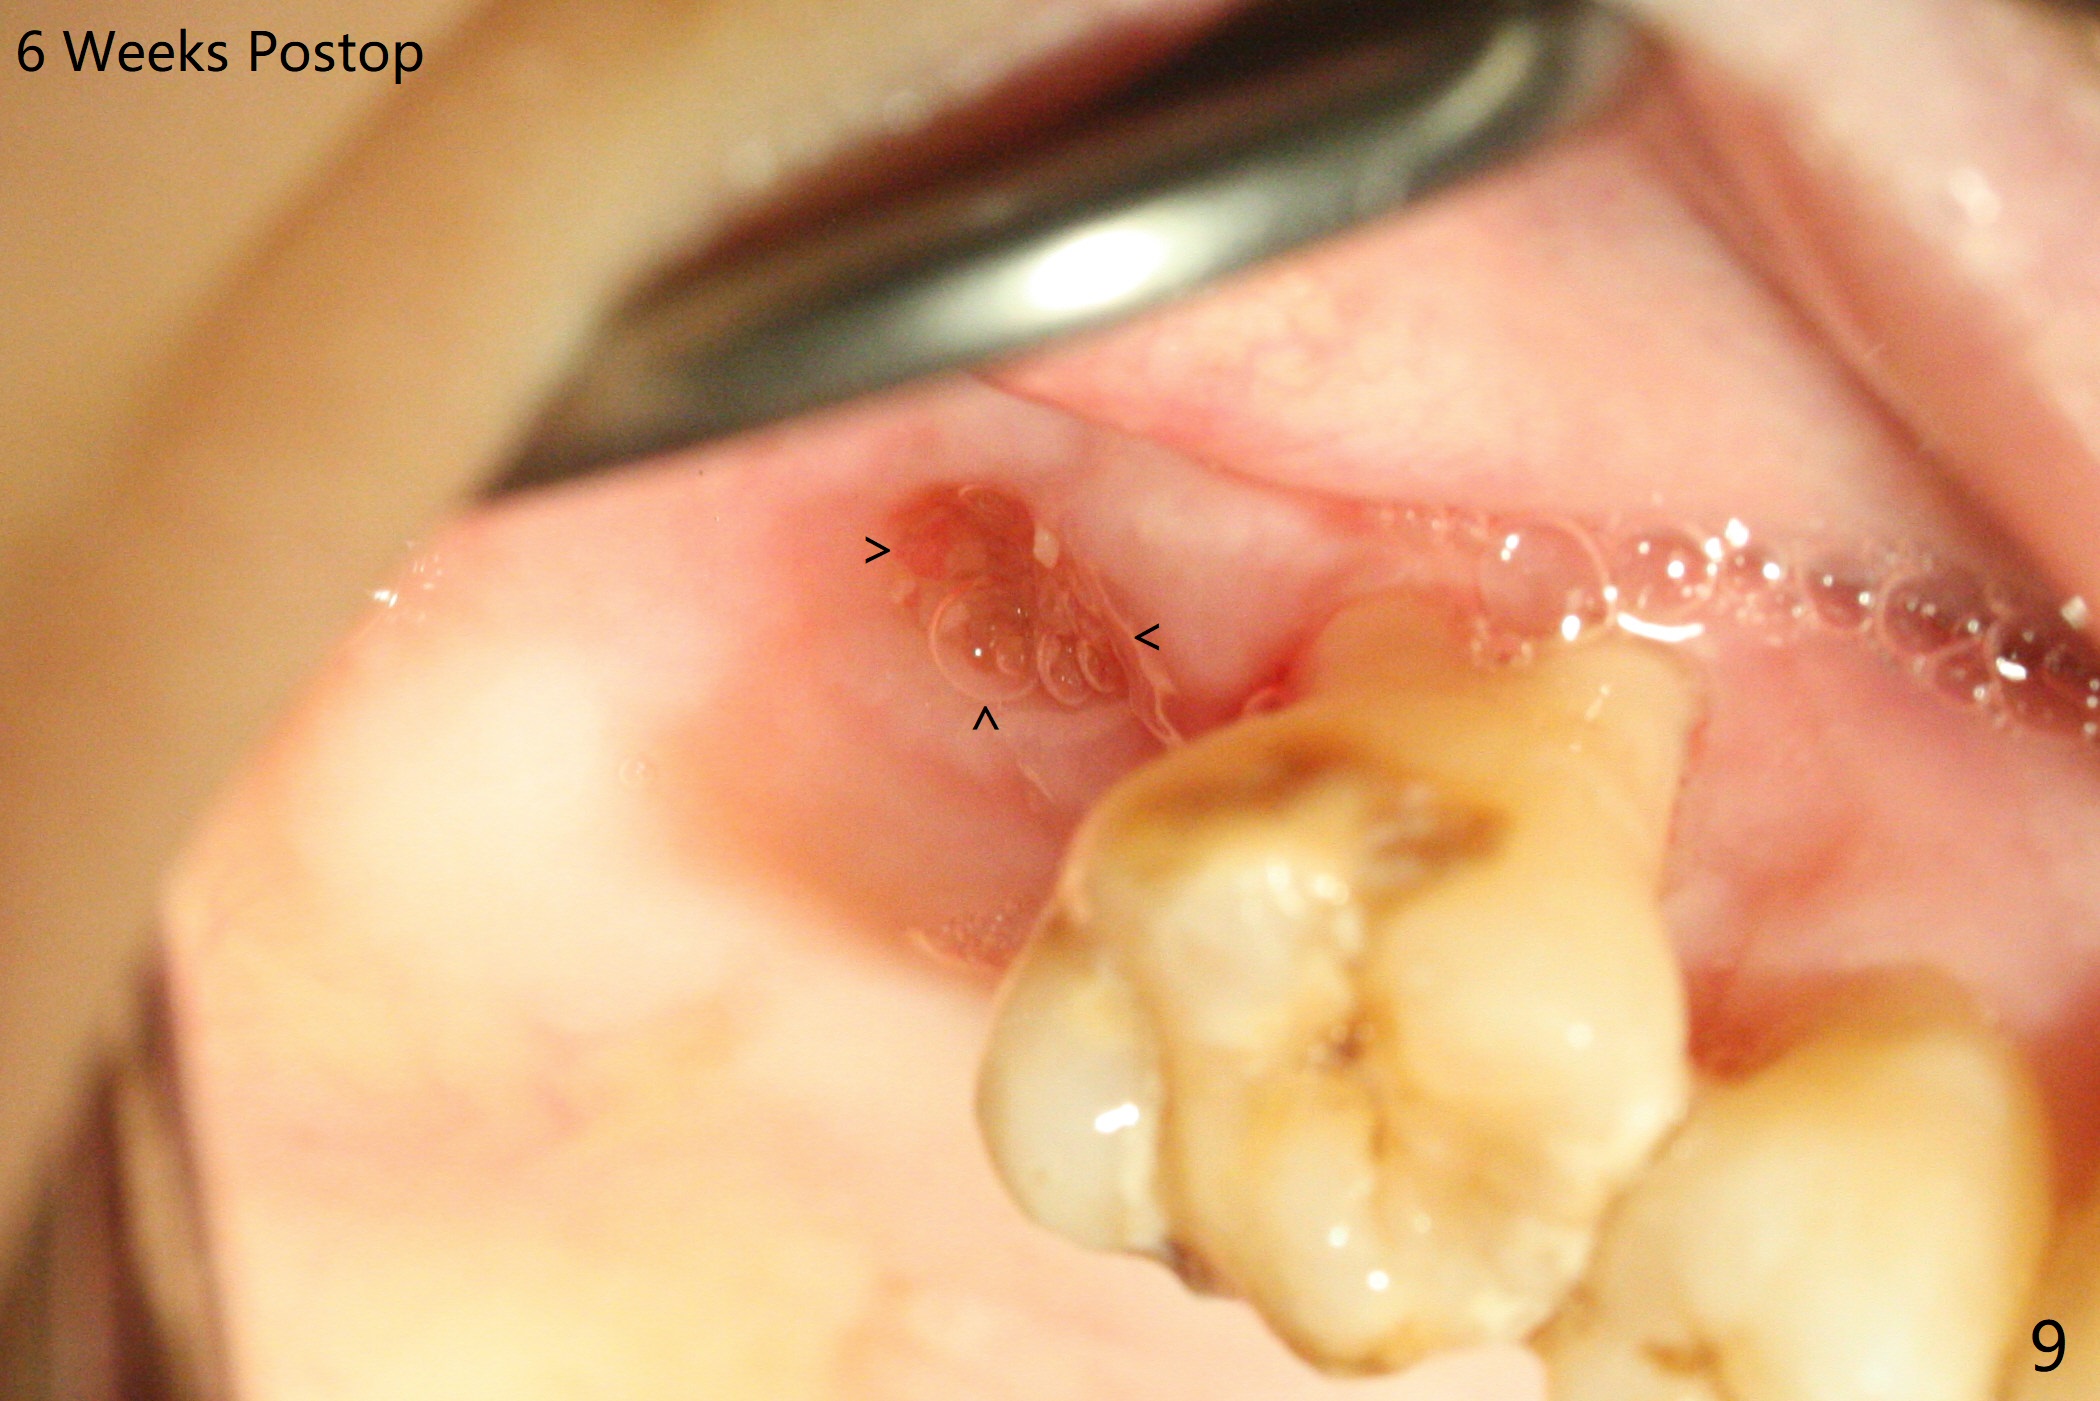

尽管右上第一,二磨牙骨质吸收严重,为了保持牙乳头,先拔除有症状第二磨牙,但是后者牙槽窝与第一磨牙之间好像没有软组织(图二:*),所以骨粉(图一,二:7)无法从前者推入后者(图二(下一个成功病例))。骨粉表面放置6个月吸收膜(GEM Cap(图三::C)),使用牙周胶水固定,而且装置牙齿空间维持器(图二:S)和牙周敷料强化固位。牙齿拔除证实腭侧牙槽窝(图四:P)上颌窦底板穿孔(^;但是没有漏气)。虽然病人已经服用Amoxicillin一周以及Z Pack(两颗,术前),为了防止感染介入上颌窦,穿孔冠部放置胶原塞(图五:黄色),然后放置骨粉(红色)。后者仿佛增加骨质高度不少(图二)。如果不够,以后再做提升。多亏间隙保持器,牙周敷料术后4天没有松动迹象(图六)。术后三周敷料颊侧有些破裂(图七),而舌侧完整(图八)。嘱咐病人正常刷牙和水牙线,让敷料自行脱落。其实术后六周敷料仍在原位,不可吸收膜粘附于敷料,两者一起去除,伤口愈合(图九),骨粉好像没有损失(图十)骨高度减少。术后4个月骨质高度继续减少(图十一)。植骨后骨质高度还与邻牙一致,密度低,可植入5x7.3毫米植体(图十二)。